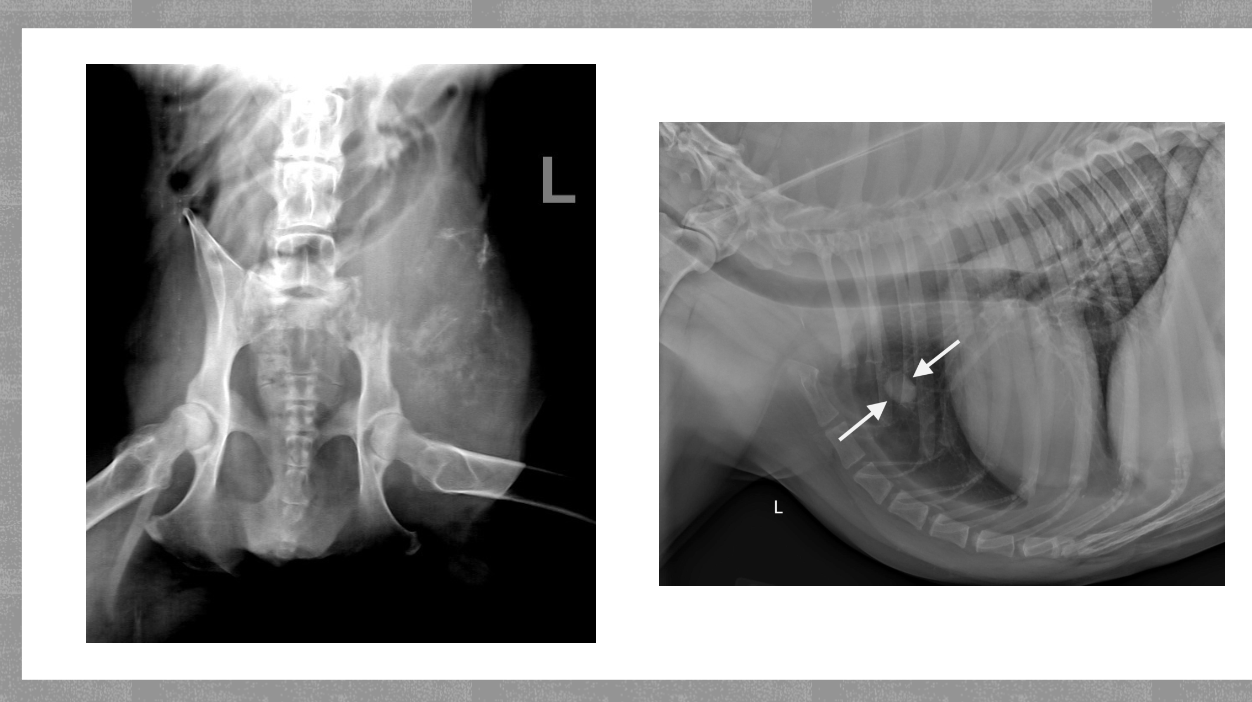

Hip dysplasia what happens

Malformation and degeneration of the coxofemoral joint

HD what does it look like of radiographs

Flattened femoral head

Thickened femoral neck

Shallow/ sclerotic acetabulum

Numerous osteophytes